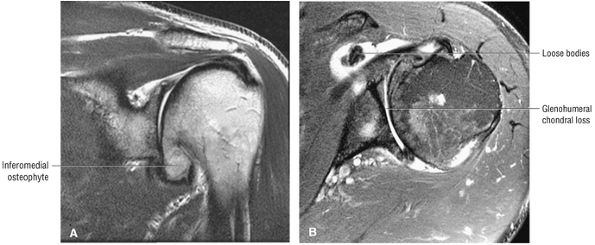

Glenohumeral articular cartilage follows the concave shape of the glenoid cavity and demonstrates intermediate signal intensity on T1-weighted images and bright signal intensity on T2*-weighted images. Articular cartilage of the glenoid margin of the anterior labrum may be mistaken for a tear. Articular cartilage of the glenohumeral joint is better evaluated on FS PD-weighted FSE sequences.

At the lateral angle of the scapula is the glenoid cavity (glenoid fossa) with its supraglenoid and infraglenoid tuberosities. The glenoid version angle varies and may contribute to instability patterns of the shoulder.